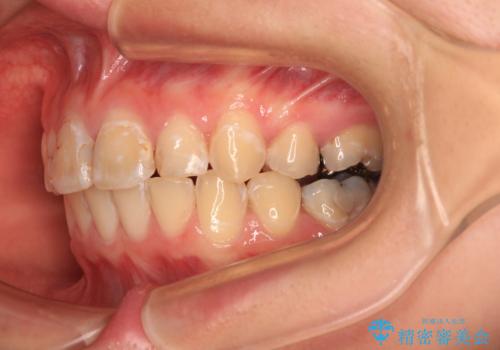

- 上の前歯の出っ歯とでこぼこの歯並びを気にして来院された患者様です。

上下顎歯列ともに前方に突出していましたが、上顎歯列がより前方位にあったため、上顎左右は第1小臼歯を、下顎左右は第二小臼歯を抜歯することとしました。

目立たないワイヤー装置にて抜歯矯正を行うこととしました。